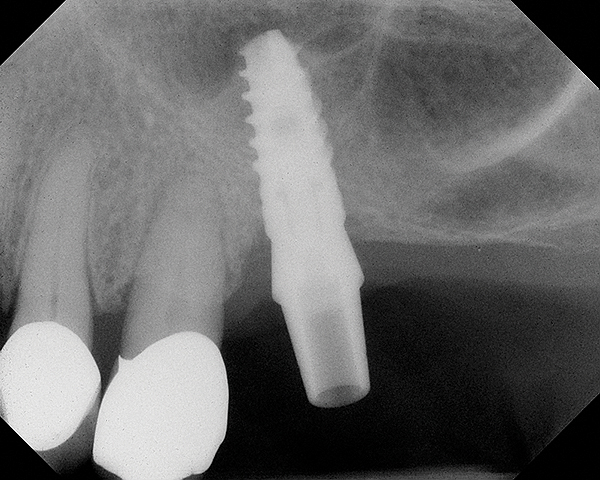

Fig 15. Radiograph of implant No. 14 with sinus augmentation, day of placement. The floor of the sinus has been raised about 7 mm to 8 mm.

Figure 15